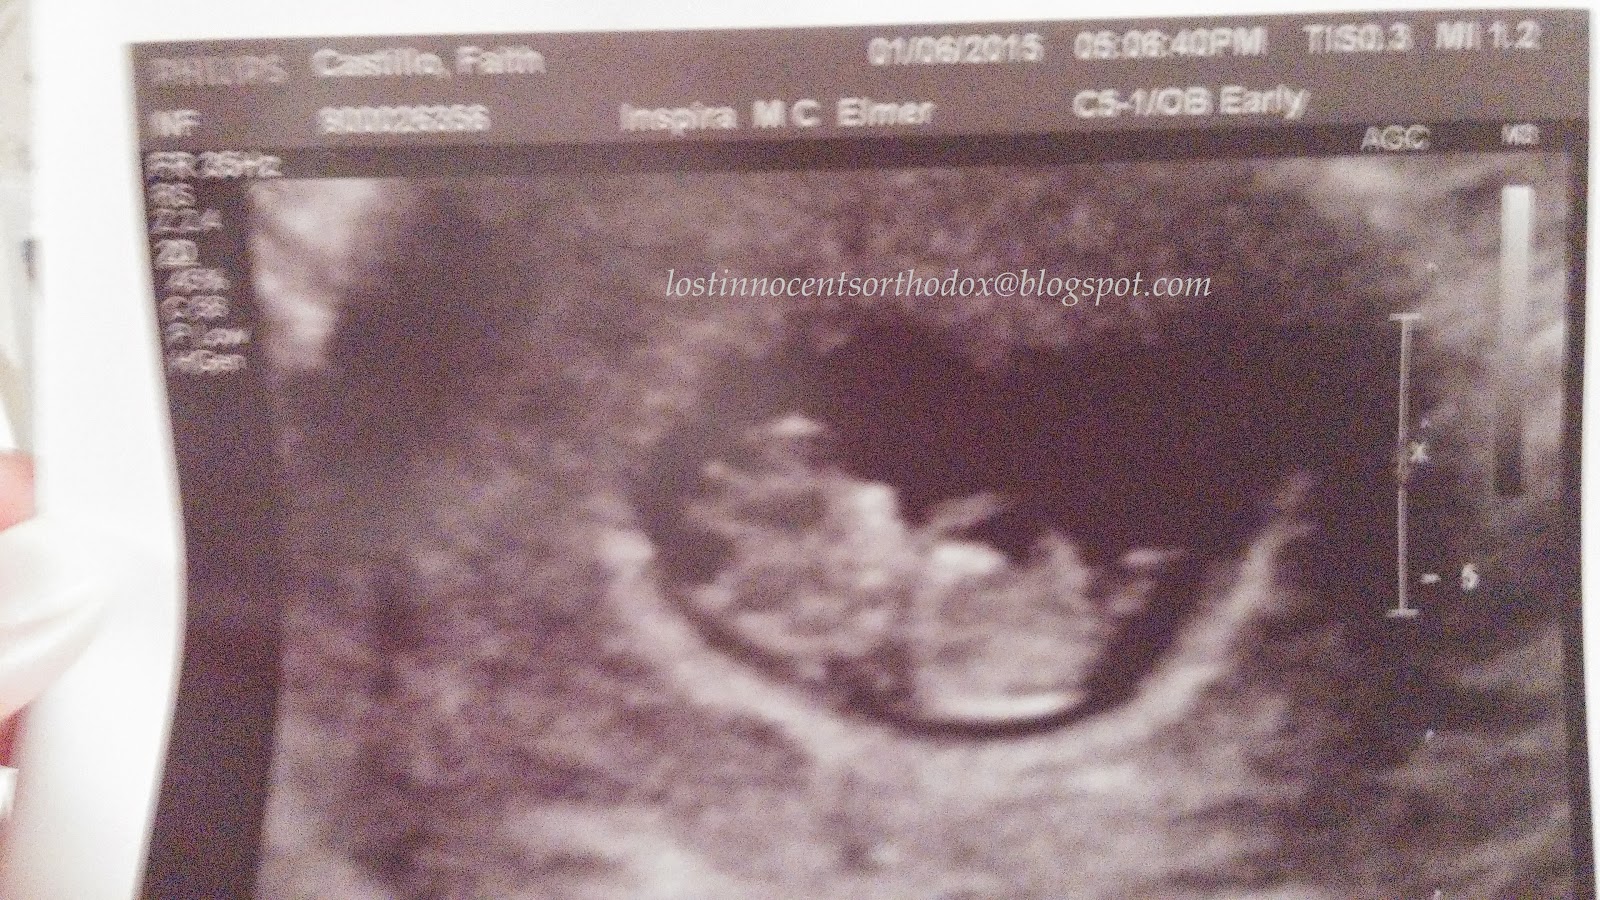

Nicki’s story of her missed miscarriage at 6 weeks 2 days, discovered at 10 weeks, 5 days, miscarried at 11 weeks, 2 days. Born at home on the eve of Forgiveness Sunday.

At the beginning of January 2015, we learned I was pregnant. My husband and I had been trying for 12 months since the loss of our first, due to an ectopic pregnancy I experienced just weeks after we got married. I had surgery to remove one of my tubes, and lost our first precious baby on October 1, 2013. I named him shortly after discovering your website “Protection”, as he was delivered on the Feast of the Holy Protection of the Theotokos. I was approximately 6wks 4 days at the time. When I got pregnant with our second (I named her “Forgiveness”), I was elated! I remember taking the pregnancy test that morning in our bathroom home alone (for probably the 30th time in the last 12 months), thinking it would be another negative result. When a saw the second line come up and realized what wonderful miracle had happened, I remember I just looked up at the ceiling and said “Thank you Lord” through tears of joy. As a precaution, I had an ultrasound to confirm that our baby was in my uterus (that was done at 5 wks 2 days), as I was at a higher risk of experiencing another ectopic. I had a gut feeling that this was a little girl. I was so sure, but did not know why. With the first pregnancy I did not have any such gut feeling, so I decided that my first must have been a boy. Only God really knows I guess.

The weeks that followed were wonderful, I had a perma smile as they say. During my sixth week, we had our parish priest come bless our home for the new year, and shared the news with him. He blessed my tummy and instructed me to drink the holy water every morning until the birth. The weeks carried on. I was not showing any major signs of pregnancy (eg. morning sickness) except that I was getting more bloated and couldn’t fit into my work attire that well anymore….and lots of peeing in the middle of the night… On Tues. February 17th (10 wks 5days), I learned through ultrasound that there was no heartbeat. They compared my first scan from the 5wk appointment to the new one, and determined our baby stopped growing at about 6 weeks. My doctor prescribed me 4 Misoprostol pills to take vaginally and sent me home that day.  She described to me that the bleeding would be like a very heavy period with more and larger clotting than usual. Not even close. To this day, I wonder if our baby was still alive when our priest blessed her with the sign of the cross over my tummy, or whether we should have had the priest come the week before so I would have started the holy water sooner. I know it’s wrong to think this way, I just can’t help it.